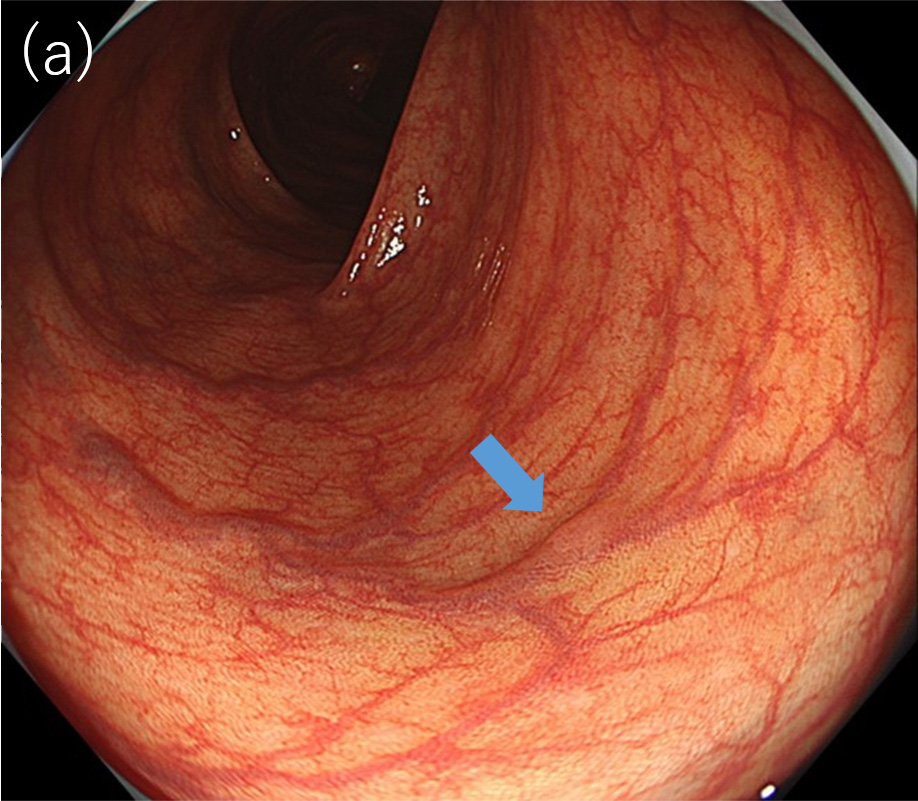

〈図1〉XZ1200による同一病変に対する中遠景観察像(a)白色光観察; (b)TXI観察(モード1)

〈図2〉 XZ1200による同一病変に対するNBI中遠景観察像(a)BAI-MAC OFF; (b)BAI-MAC ON